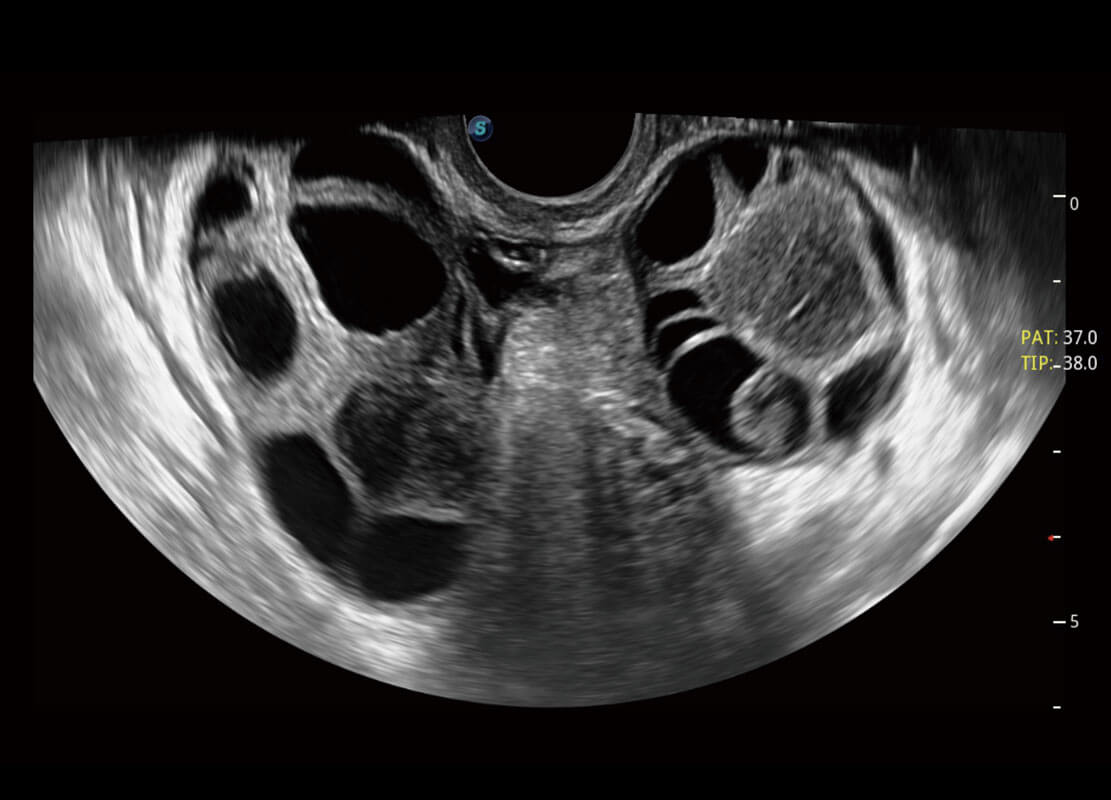

腔内妇科-卵巢

P60优异的图像质量搭载专科探头,在妇科基础疾病的诊断、卵泡生长的监测、输卵管通畅情况的判别等方面为您提供生殖应用方案。